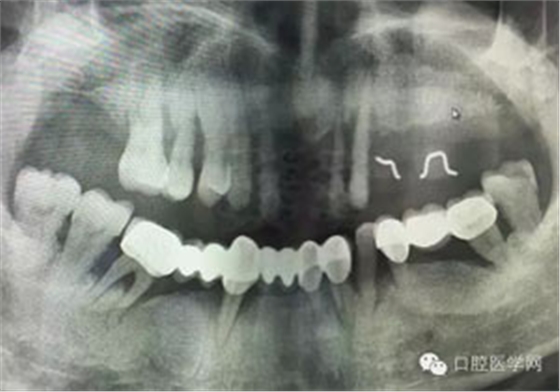

病例1:患者迫切希望保留自己的這一顆牙齒,根尖周陰影比較大,二度松動(dòng).而且旁邊有種植修復(fù)體,和患者溝通好后,治療好后觀察一個(gè)月后冠修復(fù),因?yàn)橛蟹N植的后期修復(fù),所以有了機(jī)會(huì)觀察,術(shù)后三個(gè)月和術(shù)后四個(gè)月,根尖恢復(fù)的還算不錯(cuò),希望能夠繼續(xù)觀察下去.這樣子的病例,做的時(shí)候我們一定要非常的小心,和患者要有充分的溝通以及不同科室的溝通然后決定怎么樣做比較好,假如就是出現(xiàn)了問(wèn)題,到時(shí)候我們也比較好處理些,免得我們自己到時(shí)候不好收?qǐng)觥?/span> 病例2:364647中齲的樹(shù)脂充填,現(xiàn)在樹(shù)脂的充填材料非常之多,有些時(shí)候,我們感覺(jué)有了好的材料我們就可以做出好的修復(fù),可是這是在我們有扎實(shí)的基本功的基礎(chǔ)上的,我們可以沒(méi)有那么好的樹(shù)脂,那么多的顏色選擇,修復(fù)的那么的逼真,但是我們至少要恢復(fù)患者牙齒的功能,將腐質(zhì)去除干凈,薄壁弱尖消除掉,選擇好適應(yīng)癥,給患者以盡可能好的修復(fù)。 來(lái)源于KQ88